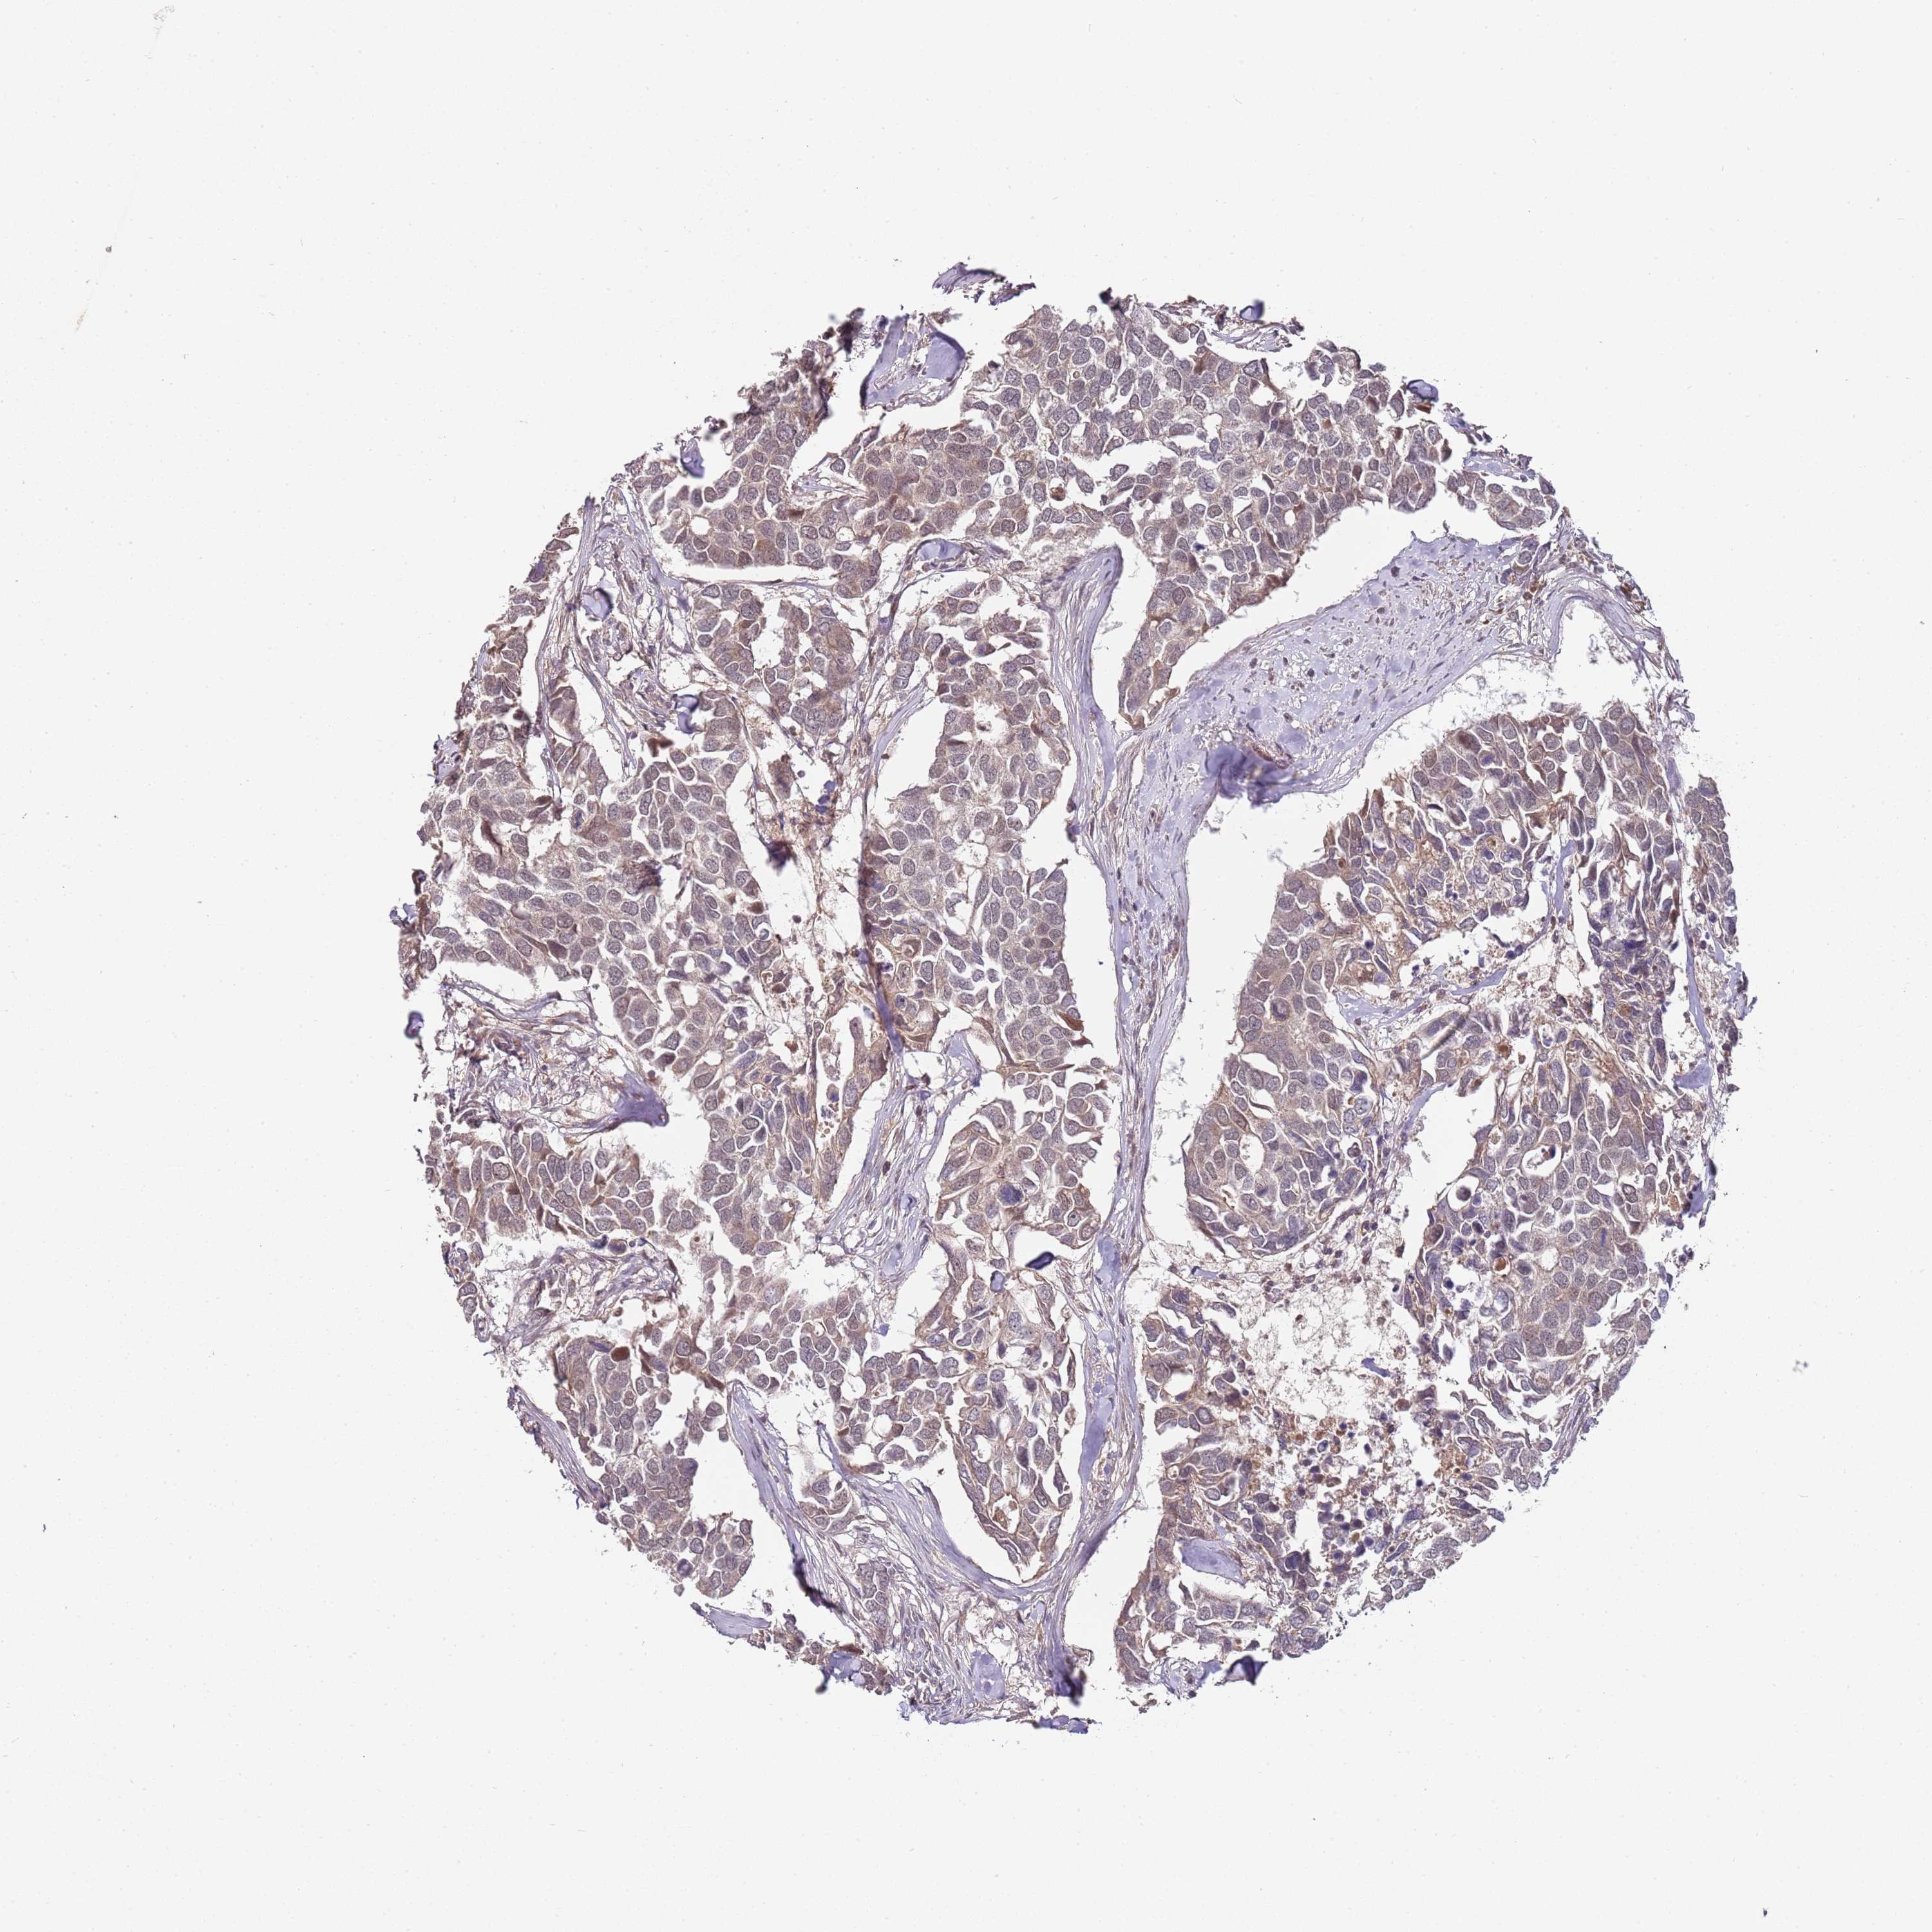

BRCA TCGA BRCA VALIDATION PROTEIN EXPRESSION

ANTIBODIES

AND

VALIDATION